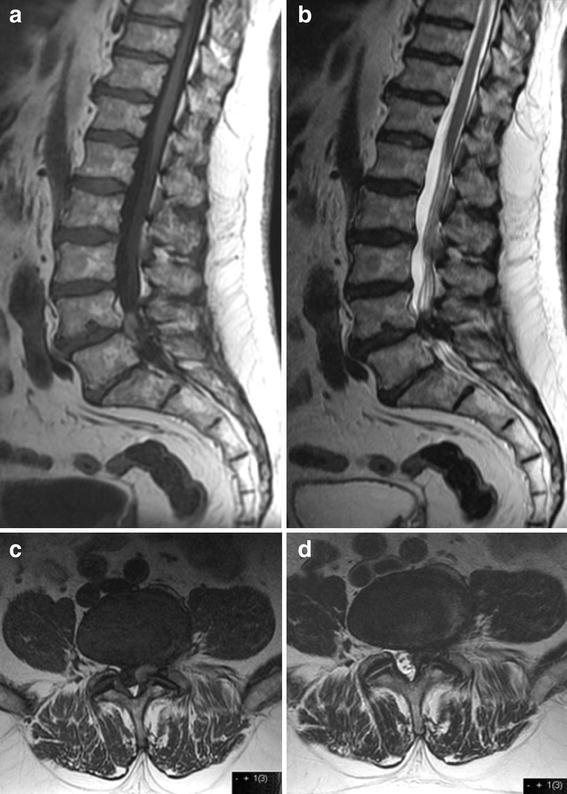

Case description: We present a case of a warfarin treated patient with left L5 radiculopathy. MRI was evaluated as showing a lumbar disc prolapse or synovial cyst at L4-L5 level. The patient was operated and an organized material was removed and analysed as a hematoma. No prolapsed disc or synovial cyst was found. The patient was neurologically restored following the operation.

Discussion and evaluation: This case illustrates how spontaneous epidural spinal hematomas can present with symptoms of radiculopathy and radiologically be misinterpreted as a protruding disc or cyst.